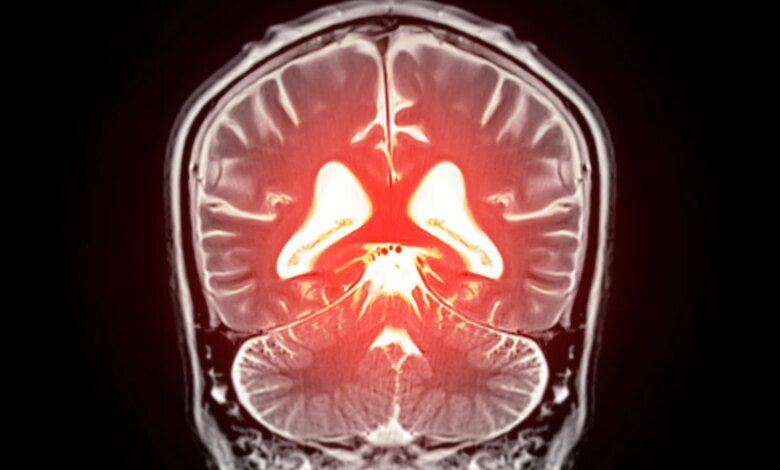

جزيء دماغي مفقود قد يكون السبب وراء الإصابة بالخرف الوعائي

قد يؤدي استبدال الدهون المفقودة في الدماغ إلى تهدئة الأوعية الدموية المفرطة النشاط واستعادة تدفق الدم الصحي، مما يفتح طريقًا جديدًا نحو علاج الخرف.

بدأ يتبلور نهج جديد محتمل لعلاج انخفاض تدفق الدم في الدماغ وبعض أشكال الخرف. كشف علماء في جامعة فيرمونت، روبرت لارنر، دكتوراه في الطب بكلية الطب، تفاصيل جديدة حول كيفية تنظيم تدفق الدم في الدماغ وحددوا استراتيجية يمكن أن تساعد في تصحيح المشاكل في الأوعية الدموية في الدماغ. تم نشر بحثهم قبل السريري اليوم (22 ديسمبر) في وقائع الأكاديمية الوطنية للعلوميشير إلى أن استعادة الفسفوليبيد المفتقد في مجرى الدم قد يساعد في تطبيع تدفق الدم العقلي وتخفيف الأعراض المرتبطة بالخرف.